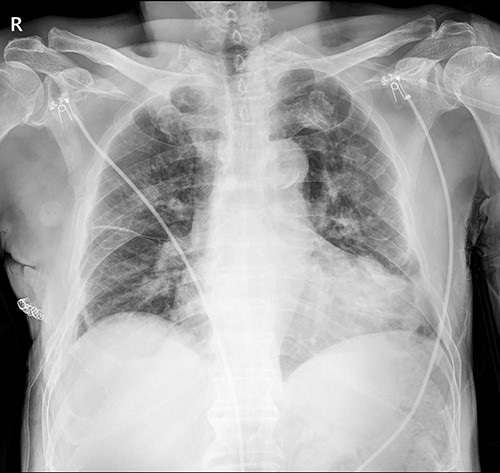

The submuscular emphysema, however, was increased in size, and the patient was eventually re-hospitalized. A small incision was made beneath the surgical wound under local anesthesia, and a 10 FR thoracic drainage catheter was carefully placed into the submuscular layer (Fig. 4.). Under 2 L of oxygen supplement, the submuscular emphysema gradually decreased over several days, and the patient was finally discharged on hospital Day 6 (Fig. 5). Since his last readmission, there have not been any more complications.

Chest X-ray after applying a 10 FR drainage thoracic catheter into the submuscular layer (11 March 2022).